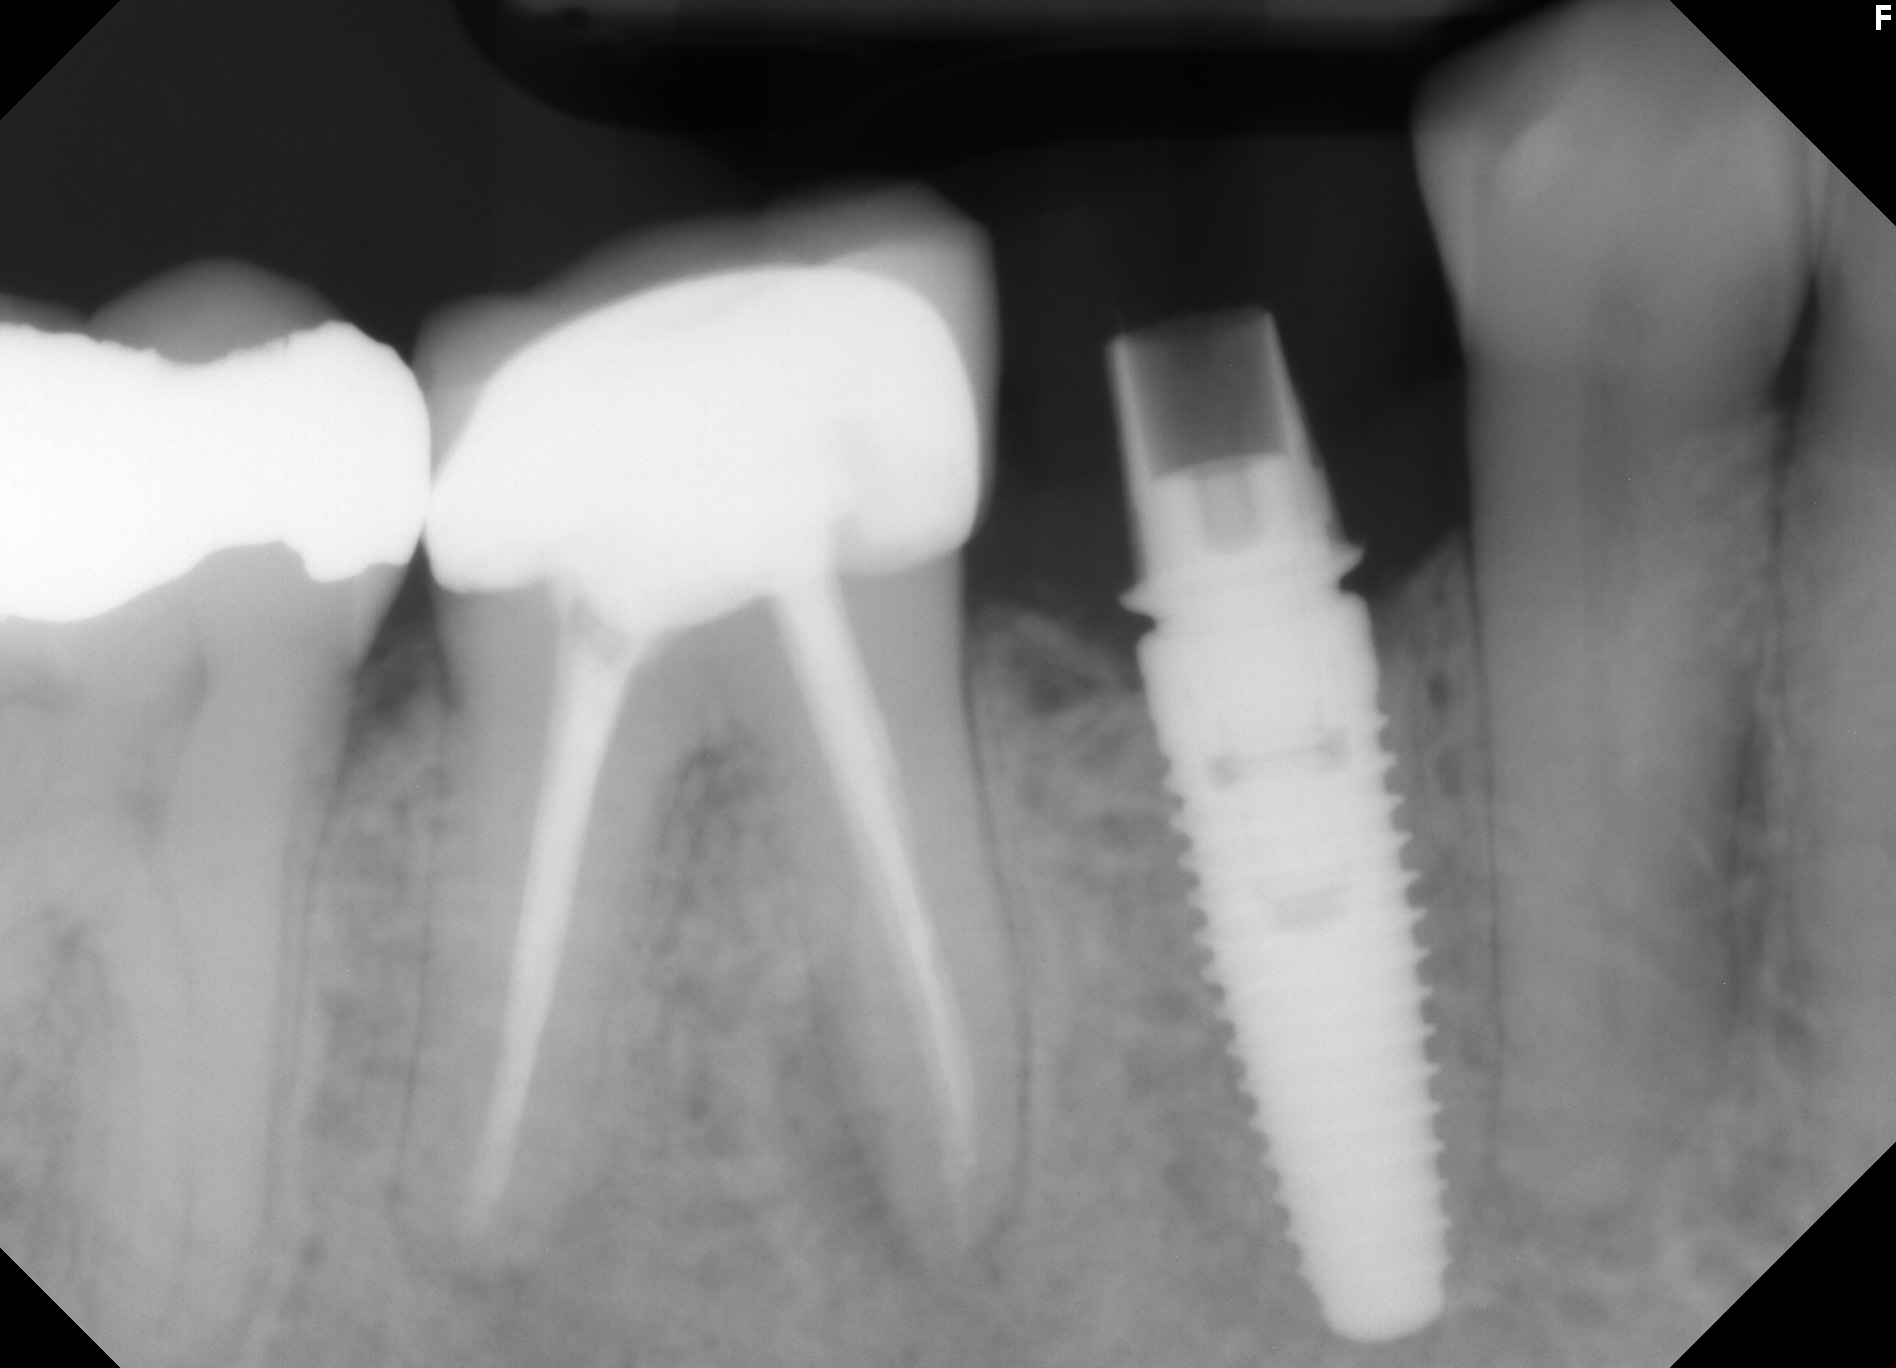

Results: This alternative CAD/CAM fabrication method was successfully used in a number of clinical cases with excellent results (see images). Although the milled portion of the crown accommodated the TiBase, it did not fit as precisely as that achieved with the normal procedure using an A16 block and scanning utilizing a scan body. However, after cementation good retention was achieved between the TiBase and the milled provisional restoration.

Conclusions: Although, it is suggested that a screw-retained provisional implant resin restoration cannot be fabricated using the Compact Milling Machine, the present authors were able to develop a successful work-around protocol for fabricating a screw-retained implant provisional crown using a 40 mm Telio® CAD Bridge Block, instead of the normally utilized A16 block. For those clinicians who have not upgraded and still use a Compact Milling Unit, the present authors offer an innovative CAD/CAM process to fabricate a provisional resin implant crown.